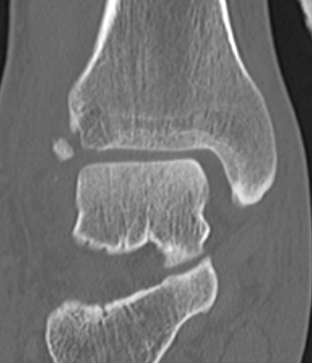

Mason and Malloy Classification

CT scan critical to classify and guide treatment / approach

| Type I | Type IIA | Type IIB | Type III |

|---|---|---|---|

| Avulsion of the PITFL |

Posterolateral fragment Volkmann fracture |

Posteromedial & posterolateral fragments Volkmann plus secondary fracture line |

Large coronal plane fragment Plafond fracture |